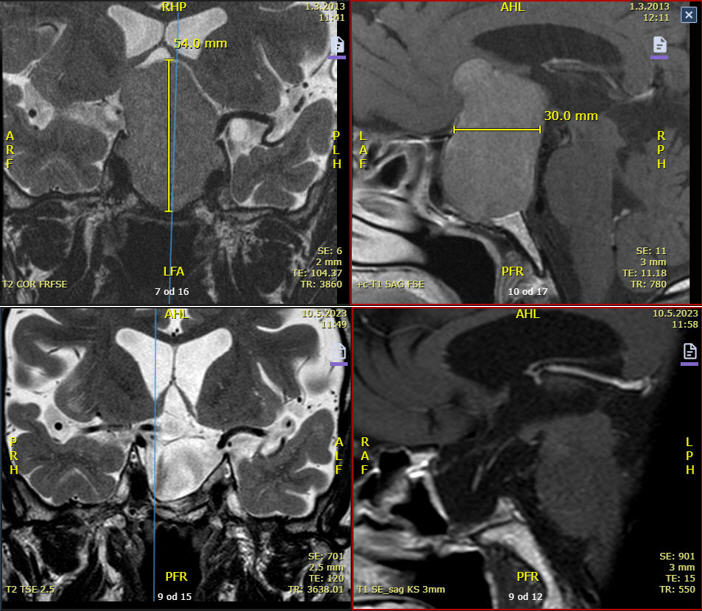

Na področju žilne nevrološke patologije ima profilaksa velik pomen in vključuje osveščanje glede načina življenja, prehrane, razvad, kot so kajenje, uživanje alkohola in uporabe nedovoljenih substanc ter preventivne preglede. Ključnega pomena je prepoznava in zdravljenje dejavnikov tveganja, kot so previsok krvni tlak, sladkorna bolezen in hiperlipidemija. V okvir preventive spadajo tudi preiskave, npr. ultrazvok precerebralnega (karotidnega in vertebralnega žilja), ki omogoča zgodnje odkrivanje karotidne bolezni z ali brez pomembnih zožitev arterij na vratu. Zožitve karotid je mogoče zdraviti z znotrajžilnimi posegi, in sicer še pred pojavom infarktnih stanj, s čimer lahko preprečimo velike postinfarktne okvare možganov s posledičnimi invalidnostmi ali celo smrtnimi posledicami.

Od leta 1995 do 2012 je bila zaposlena na Nevrološkem oddelku v SB Celje, kjer je bila od leta 2007 vodja Enote za možgansko kap. Istega leta je opravila tečaj UZ precerebralnega in intracerebralnega žilja, najprej v Ljubljani, nato pa pridobila s tega področja še evropski certifikat na Nevrološki kliniki v Zagrebu (Bolnica Sestre Milosrdnice).